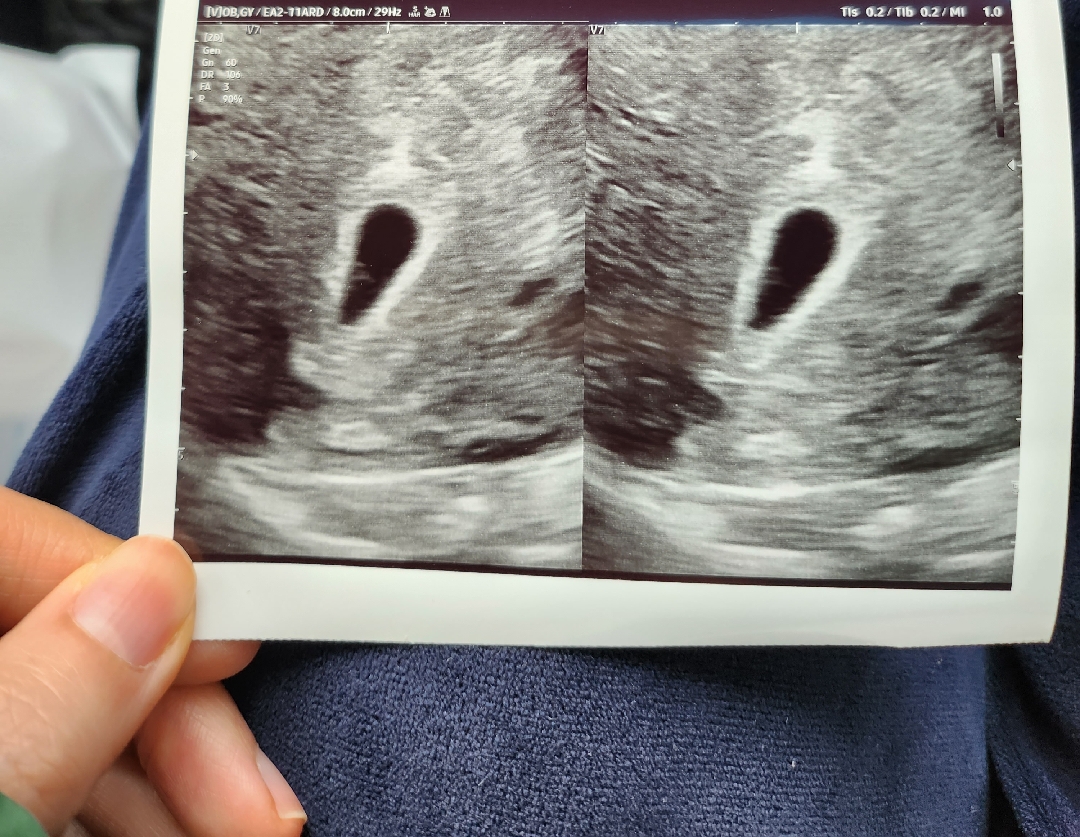

5주차 아기집 보고왔습니다~

안녕하세요 여러분 처음 글 올려봐요! 방금 병원다녀왔는데 아기집도 확인했고 난황도 보인다고 얘기해주시더라고요. 근데 아기집 크기를 여쭤봤더니 4센치라 하시더라고요.. 이제 5주차 접어들었는데 그런 크기가 나올수 있는걸까요.. 선생님이 크기를 대충재서 그러신거겠죠?ㅠ 아무리 찾아봐도 이런 크기를 가진 경우는 없는거 같아 불안하네요ㅠㅠ